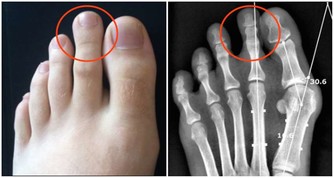

腿腳抽筋可能是因為缺乏維生素D:

說到維生素D,就要說到鈣,這兩種營養成分是非常親密的合作夥伴,

維生素D可以幫助我們機體促進鈣的吸收,

也就是說,在缺鈣的時候,要先補充維生素D,才能更好的幫助我們補鈣,

而且血液中的鈣濃度也不會因為低下,造成腿腳抽筋的現象了。

那我們應該怎麼補充呢?

最直接的辦法就是去外面曬太陽,只要曬到半個小時左右的時間,

就能夠滿足一天中人體對維生素D的需求了,但是這裡要注意的是,不要隔著玻璃或者是隔著實物曬,

這樣太陽光的紫外線才能更好的照射在皮膚上,進而形成人體所需的維生素D。